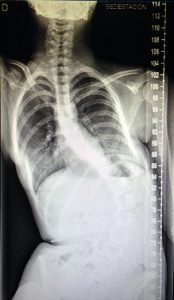

Radiografia frontal sense Spex

En realitzar una radiografia frontal es mostra l’escoliosi, que en aquest cas presenta una curvatura a la columna vertebral en forma de “S”. Això genera un plec en el costat dret de la nena, la qual cosa és un problema afegit perquè al suar es poden generar úlceres i infeccions.